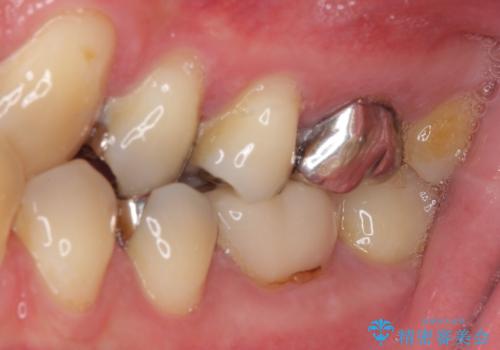

- 保険診療で装着した奥歯の白いクラウンの具合がよくないとのことで来院された患者様です。

保険診療で安価に白いクラウンが入れられるということで選択されたそうですが、装着後に痛みを感じたり、ものが挟まって不快であったりと不便が多いため、セラミッククラウンにて補綴治療を行うこととしました。

保険診療では、安価に白いクラウンを装着できる代償として、歯とクラウンの境目が不適合であったり、歯と歯の間にものが挟まりやすかったりと、不快な思いをされることがしばしばあります。

自費診療は、費用が高くなりますが、よい材料を選択したり、診療時間を十分にとったりできるため、単純に白いだけではない、良質なクラウンを装着することが可能です。